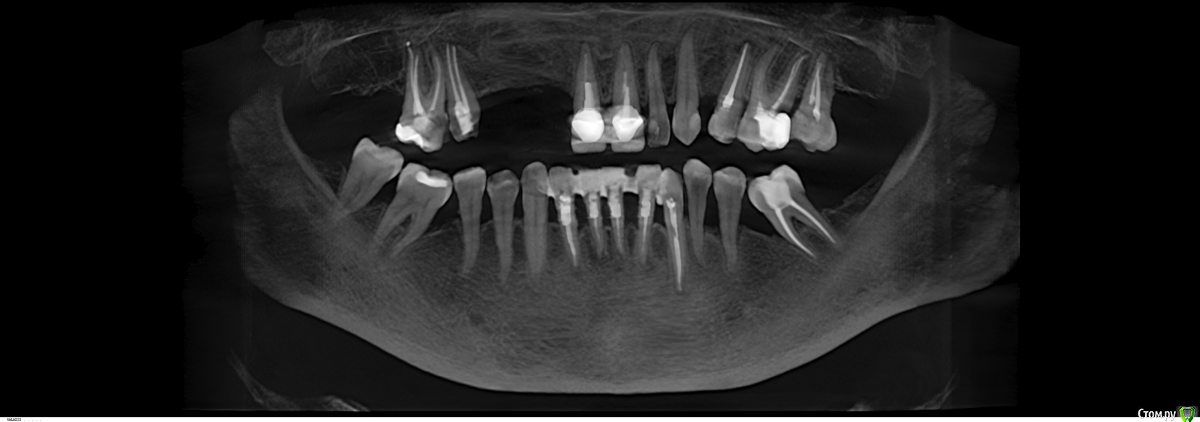

Robinbobin Опубликовано 9 сентября, 2015 Поделиться Опубликовано 9 сентября, 2015 Зуб 1.1 удалил,кюретаж и одномоментно установлен имплантат, заполнил MP3 и закрутил заглушкуУстановил имплантаты в области 1.3,1.4 подсыпал так же MP3 под мембрану и запинилЕсли покажите пальцем на ошибки буду благодарен))) 4 Ссылка на комментарий

Большой Зеленый Опубликовано 9 сентября, 2015 Поделиться Опубликовано 9 сентября, 2015 11 имплант нужно было медиальнее ставить и чуть еще утопить платформу 1 Ссылка на комментарий

Bier Опубликовано 13 сентября, 2015 Поделиться Опубликовано 13 сентября, 2015 ставить нужно учитывая шейку будущего зуба, а не глубже "потому что часть кости уйдет" Тут будет некрасивая ортопедия. 2 Ссылка на комментарий

SergeyAL Опубликовано 13 сентября, 2015 Поделиться Опубликовано 13 сентября, 2015 полностью согласен, у ортопеда будет много проблем с эстетикой из-за разного уровня шеек имплантатов. Ссылка на комментарий